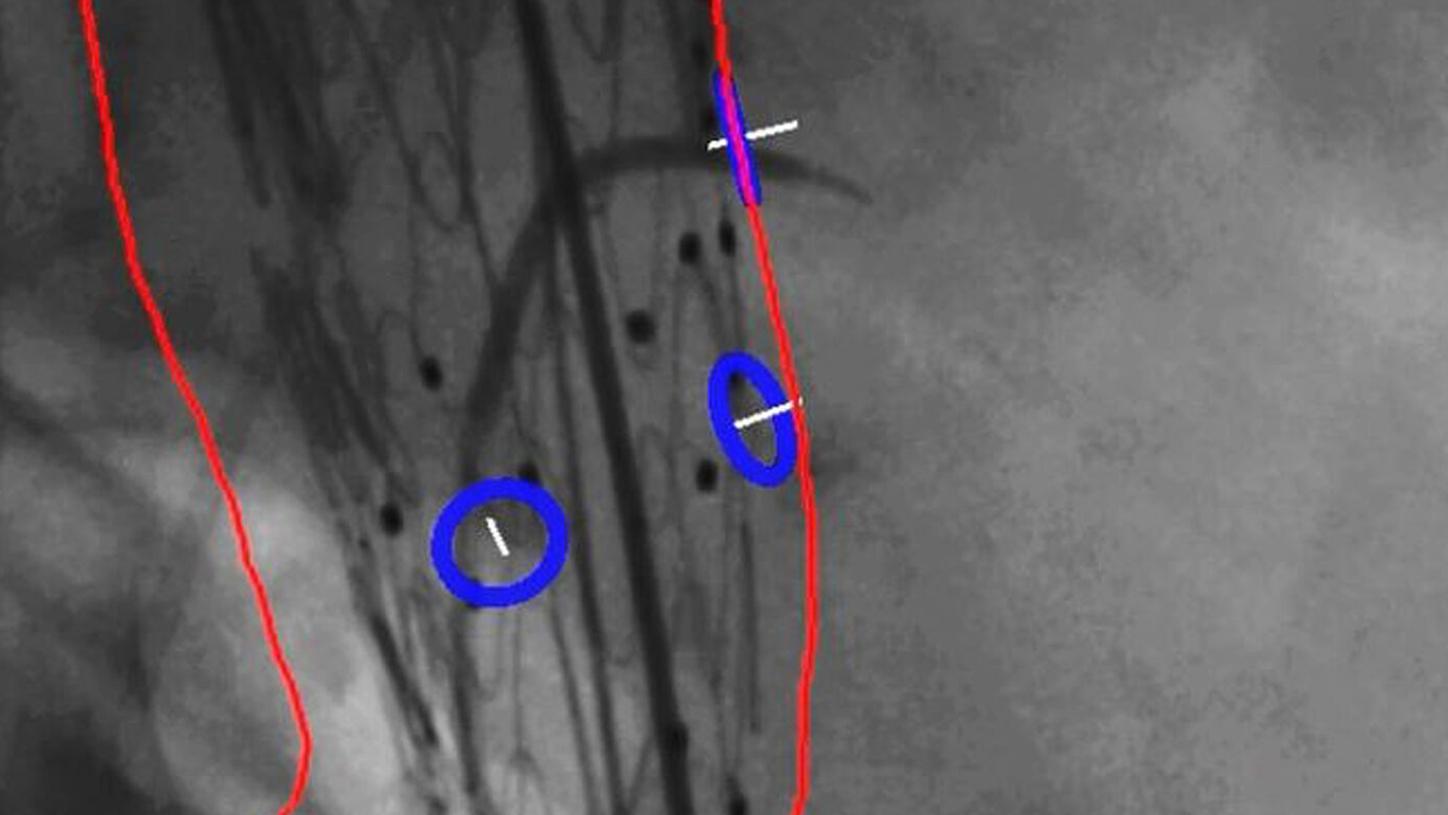

ARTIS icono Structure Scout

Material-specific imaging with Structure Scout

Structure Scout enables improved device visibility supporting ALARA dose due to material-specific optimization of imaging parameters.

With new devices and new materials appearing all the time, image-guided therapy is facing new challenges. Structure Scout adjusts the X-ray spectrum to material-specific acquisition parameters and optimizes visibility of materials, devices, vessels, and background structures independent of procedure or material type with our embedded structure-sensitive algorithm.